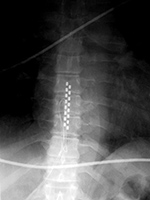

| Zero-Profile lumbar fixation L2-L5 |

| 45 year-old woman with L2-5 anterior lumbar interbody fusion (ALIF) for low back pain. The lateral views are respectively in neutral and flexion positions. The CT images are selected slices in the coronal and sagittal planes, respectively. |

| 45 year-old woman with L2-5 anterior lumbar interbody fusion (ALIF) for low back pain. |